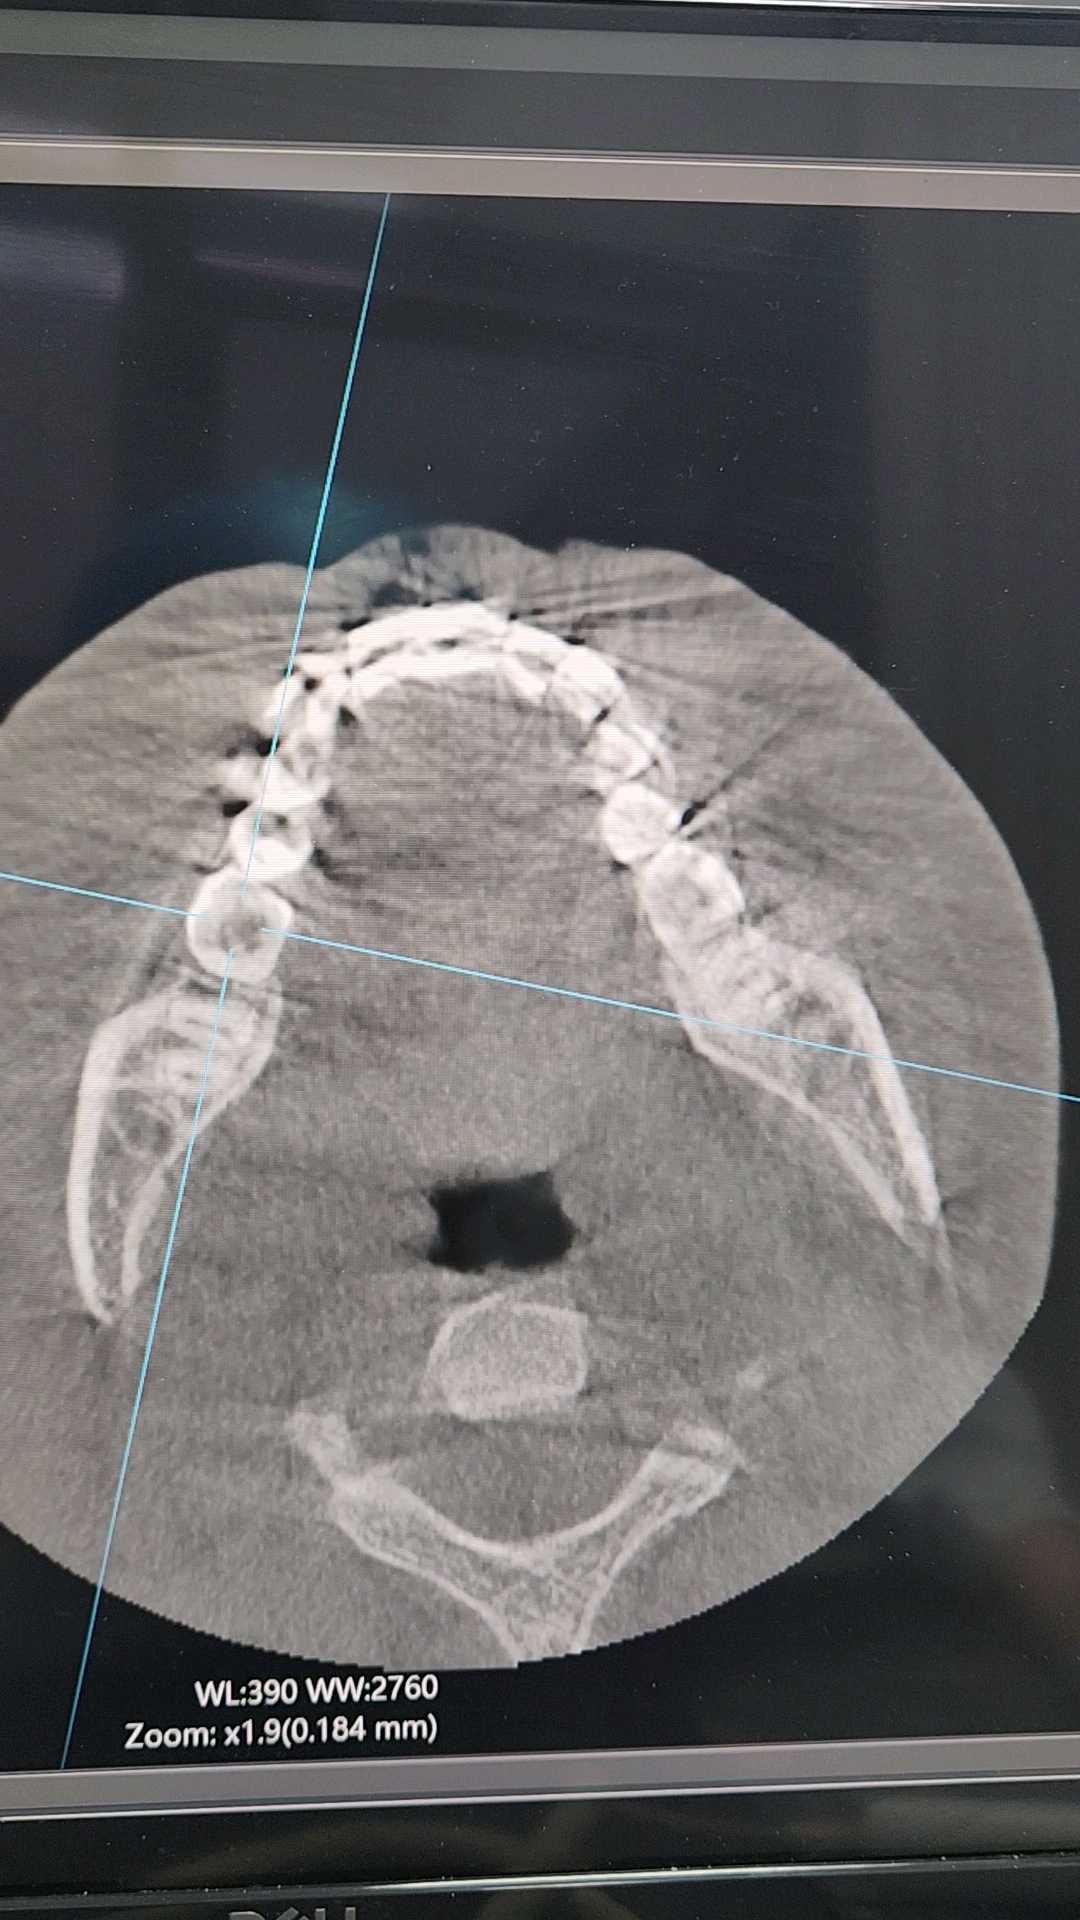

右下6是远中根折吗?

患者12岁,女,主诉右下后牙不适疼痛2周余伴夜间疼。查体见:#46颌面深龋,色黑,质软,冷刺激反应迟钝,叩++,松动度无。

口腔全景片示:#46颌面低密度龋坏影像及髓,远中根中1/2可见疑似高密度根折影像,根尖未见明显异常。

CBCT协诊。

患者否认咬硬物史。

想请教各位同仁们像根折吗?